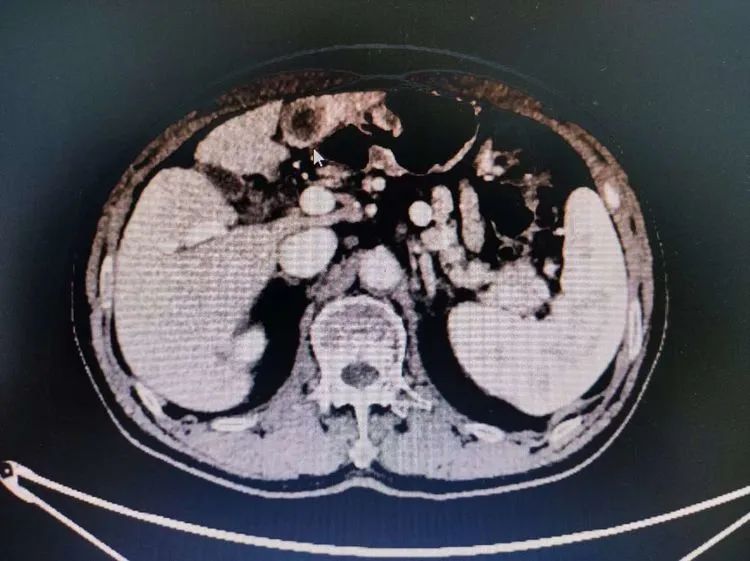

数日前,70多岁的徐大爷因腹痛就诊广济医院消化内科,结合丙肝肝硬化病史多年,CT腹部增强扫描示:肝左叶占位灶,考虑HCC(原发性肝癌)。请普外科会诊,诊断:肝占位性病变。手术指征明显,患者各项指标符合手术要求后,刚刚“阳康”的外科团队为老人顺利进行了“腹腔镜辅助下肝左叶切除术”。

“患者有慢阻肺病史,新冠感染转阴后,麻醉科卜主任和汪主任为老人全面评估肺功能和气道情况后,全麻下行手术根治性切除。今天参加手术的医护也是感染康复后的第一批。”外科顾冕主任表示,“病人不能等,条件成熟后,赶紧为他进行手术,术后病理明确系原发性肝癌。后面我们严格把控手术指征,又为其他患者进行了胆囊、疝等手术。术后恢复都很好,麻醉科团队付出很多。”